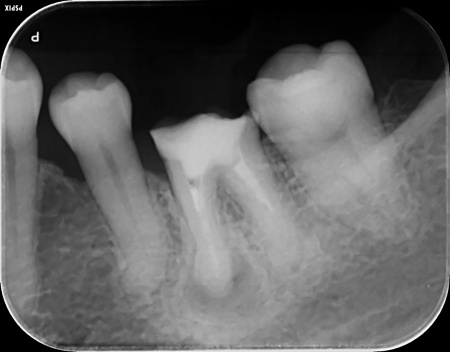

- 当院は、患者様の歯をできるだけ残し、長期的に再治療を防ぎ、質の高い健康を維持することを基本方針としています。

そのため「精密さ・耐久性・生体へのやさしさ」を重視した体制をとっており、原則として自由診療の治療をご提案しています。

一方、自由診療では個々の症例に合わせた治療設計、先進的な材料・技術の使用、再発予防を見据えた治療が可能です。